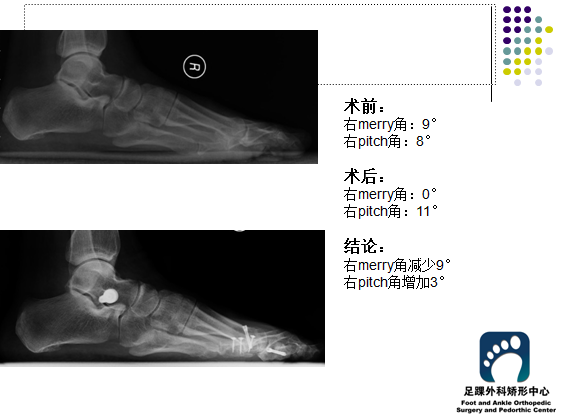

李某某,女性,55岁,主诉: 双足疼痛,踇指外偏 诊断:平足症

手术:双足距下关节稳定术 多趾截骨成形术